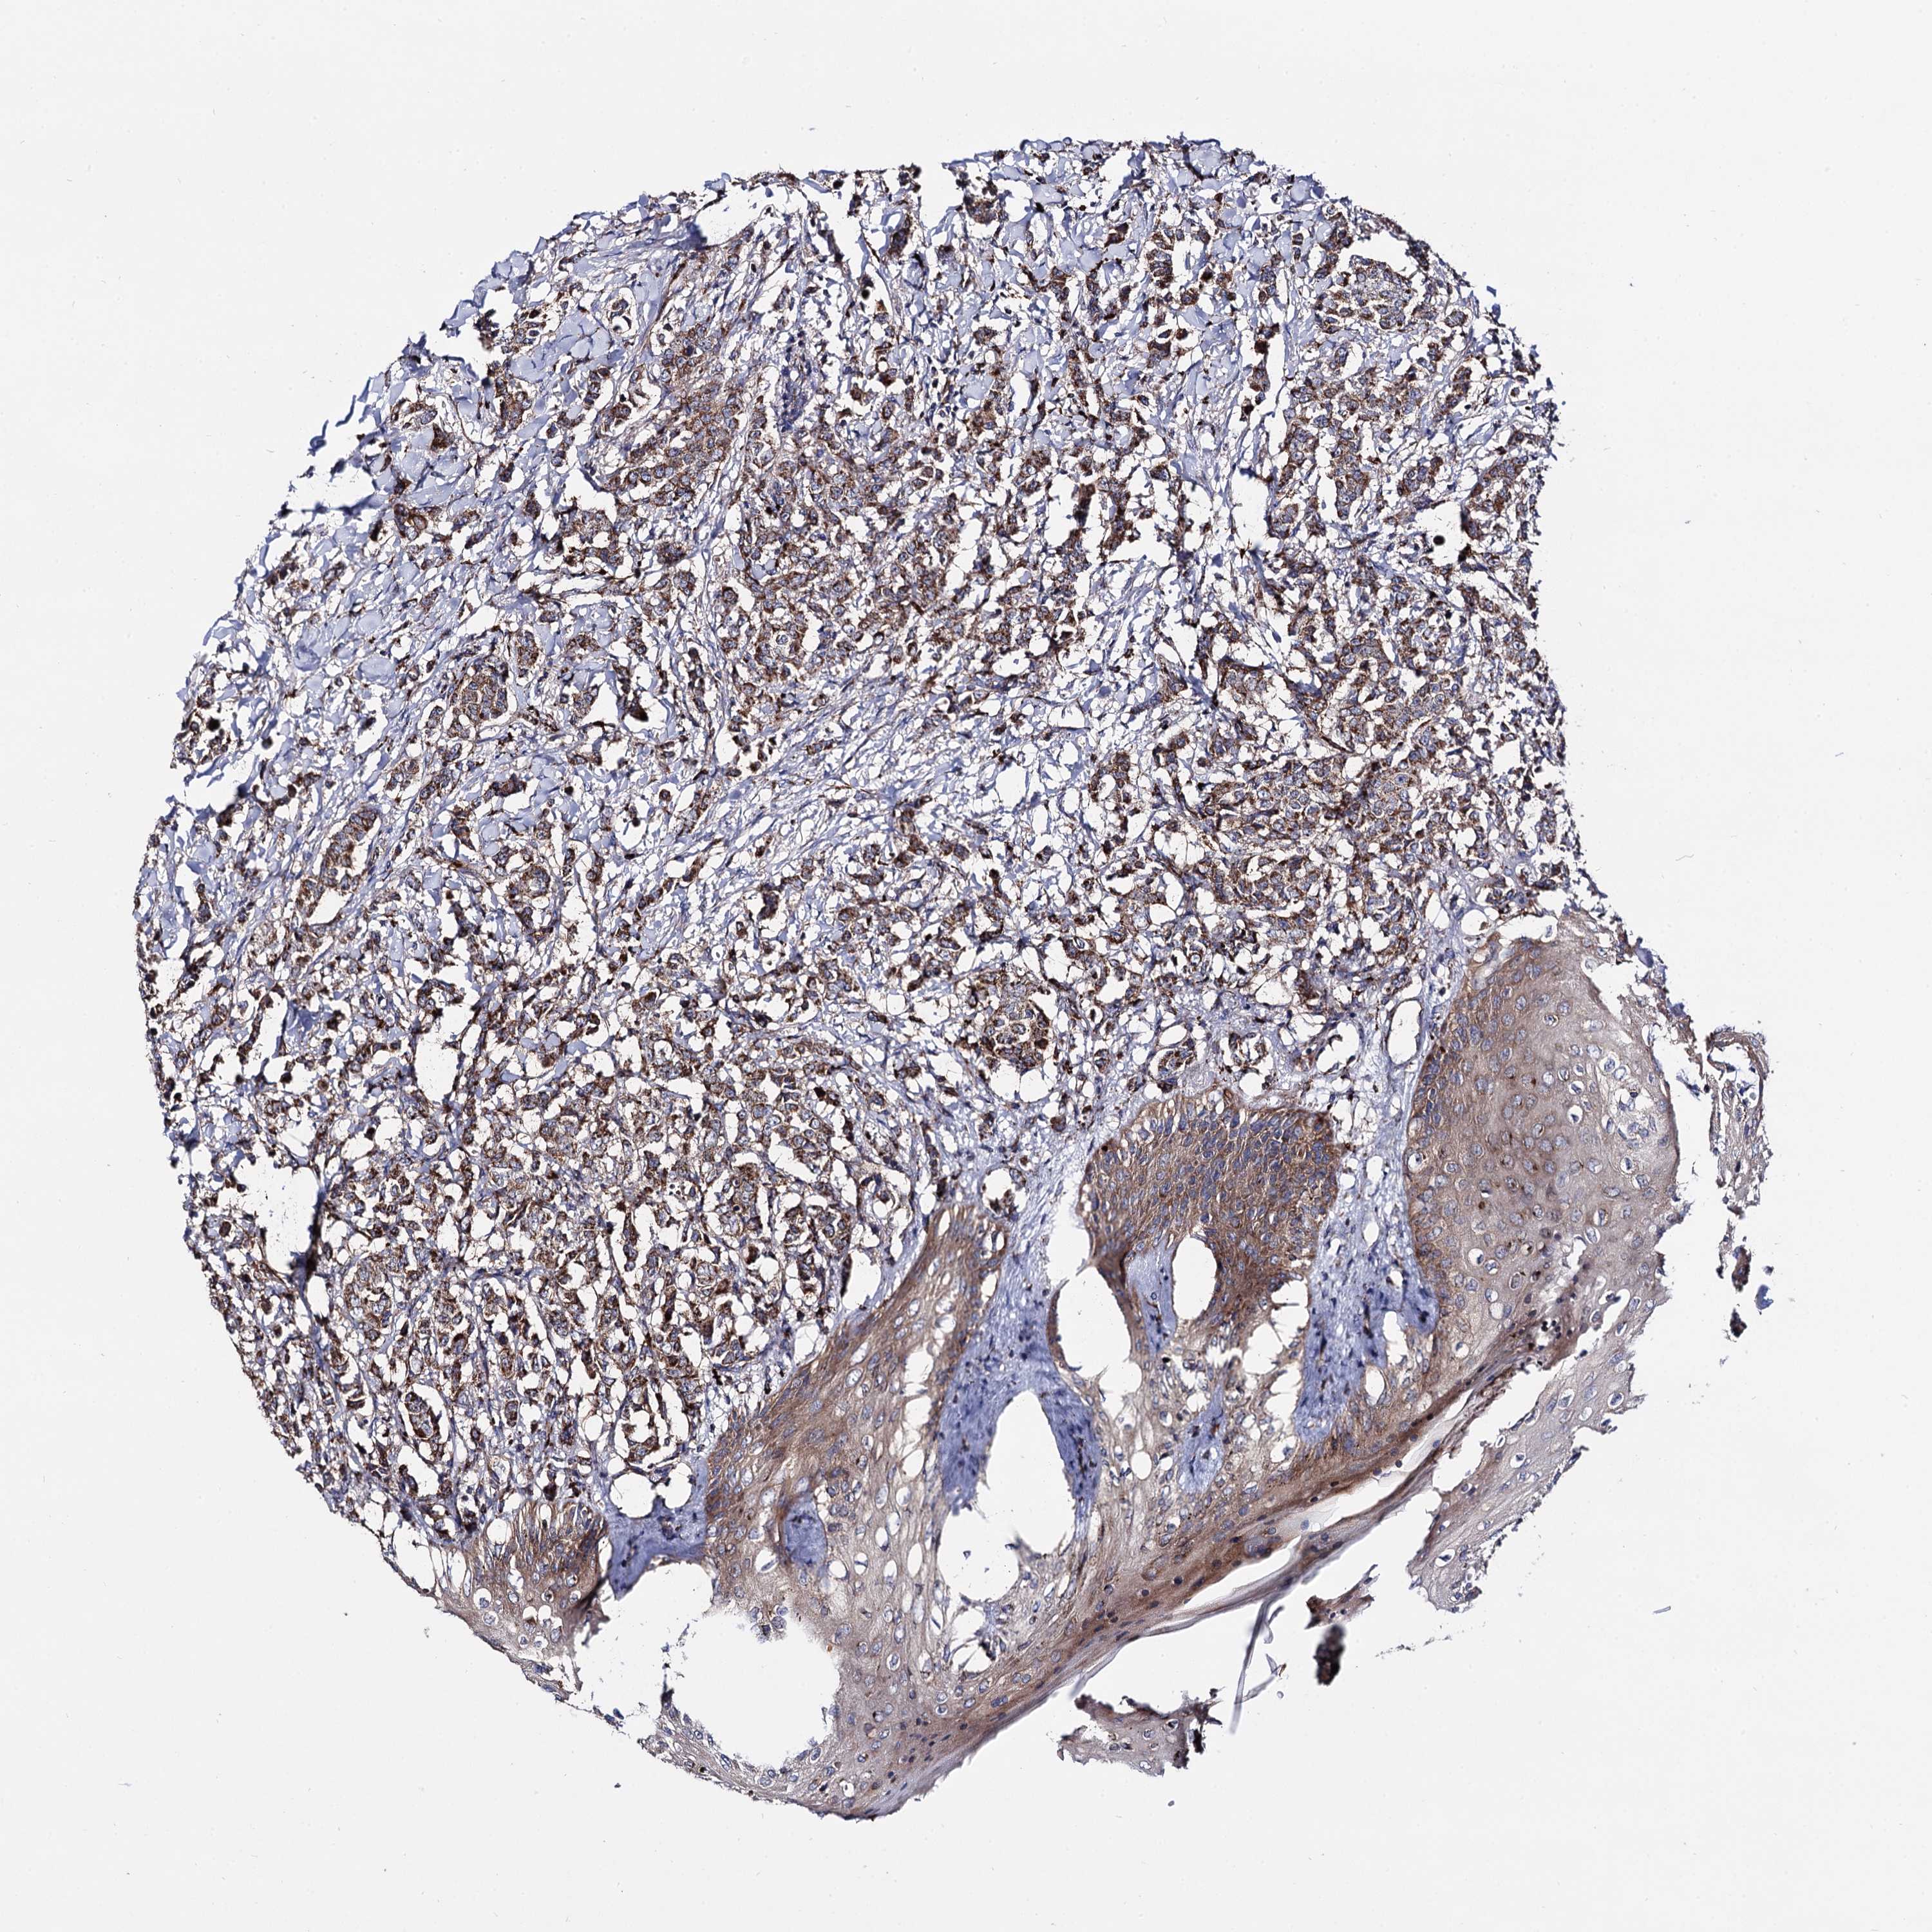

CANCER BREAST CANCER Show tissue menu

BRCA TCGA BRCA VALIDATION PROTEIN EXPRESSION